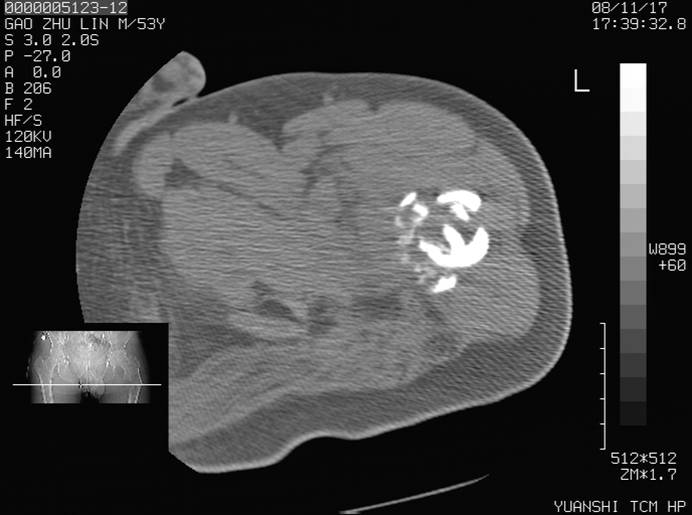

标题: CT16696:M53Y,左股骨上段骨折。 [打印本页]

标题: CT16696:M53Y,左股骨上段骨折。

左股骨上段外伤1个小时,左股骨上段疼痛。村医以腰椎间盘病变给以按摩及理疗数天。

图像不太清楚,左股骨上段外伤性骨折?病理性骨折?

左股骨上段粉碎性骨折

左股骨上段粉碎性骨折;建议上传骨窗看看是不是病理性的啊!

左股骨上段粉碎性骨折,不排除病理性骨折可能。

考虑骨肉瘤伴病理骨折

考虑:骨肉瘤伴病理骨折.

病理性骨折,考虑转移所致.

左股骨上段粉碎性骨折,不排除病理性骨折可能